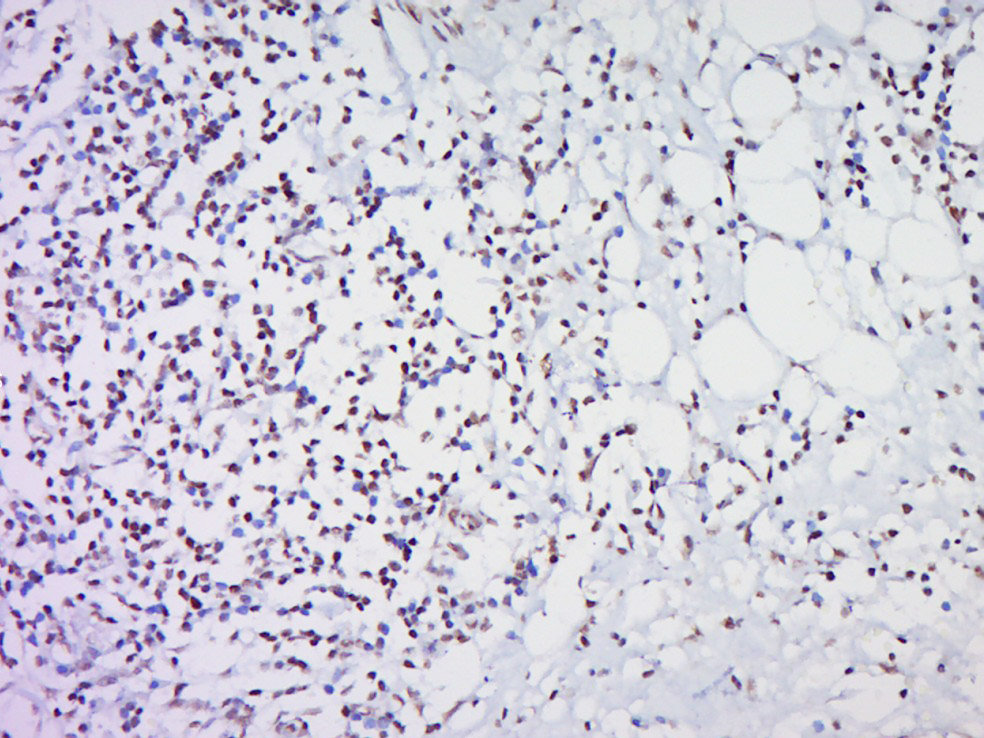

Paraformaldehyde-fixed, paraffin embedded (Human cervical cancer); Antigen retrieval by boiling in sodium citrate buffer (pH6.0) for 15min; Block endogenous peroxidase by 3% hydrogen peroxide for 20 minutes; Blocking buffer (normal goat serum) at 37°C for 30min; Antibody incubation with (Histone H3) Polyclonal Antibody, Unconjugated (bs-0394R) at 1:500 overnight at 4°C, followed by a conjugated secondary (sp-0023) for 20 minutes and DAB staining.